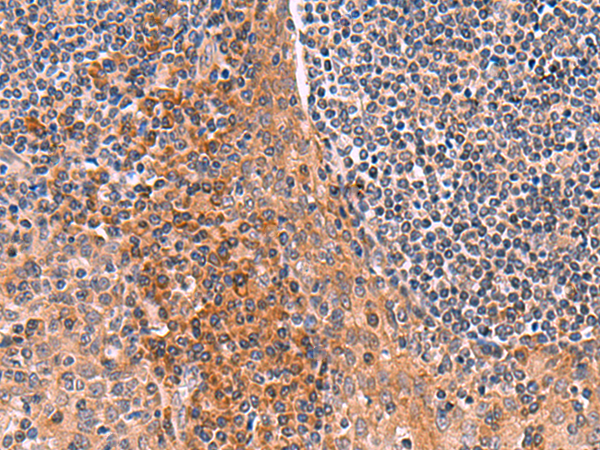

IHC positive control: |

Human tonsil |

IHC Recommend dilution: |

50-300 |